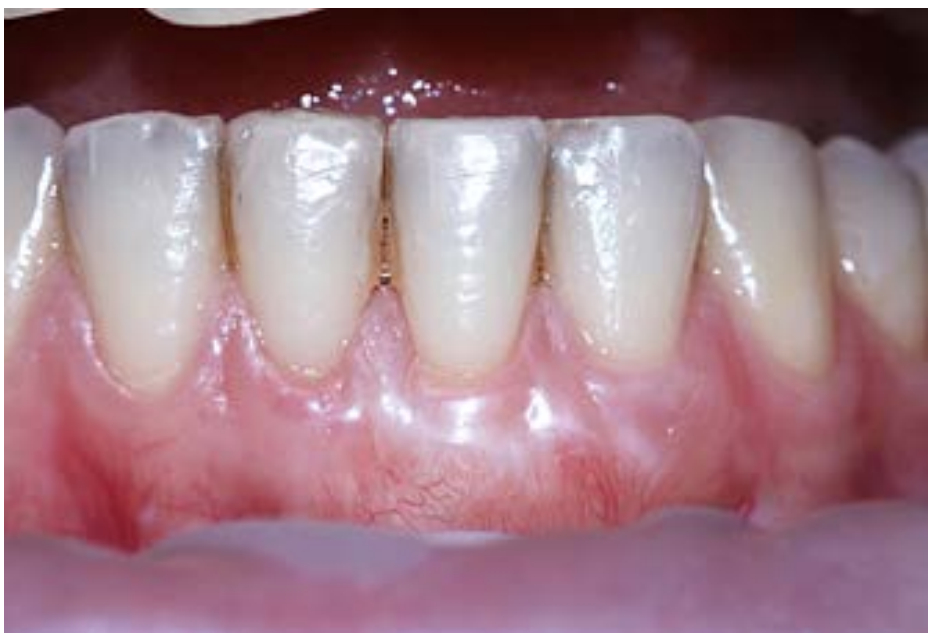

Рис. 4. Отдаленный результат лечения рецессии в области зуба 3.1 при сменном прикусе. После перемещения зуба из вестибулопозиции орально проведена пластика преддверия